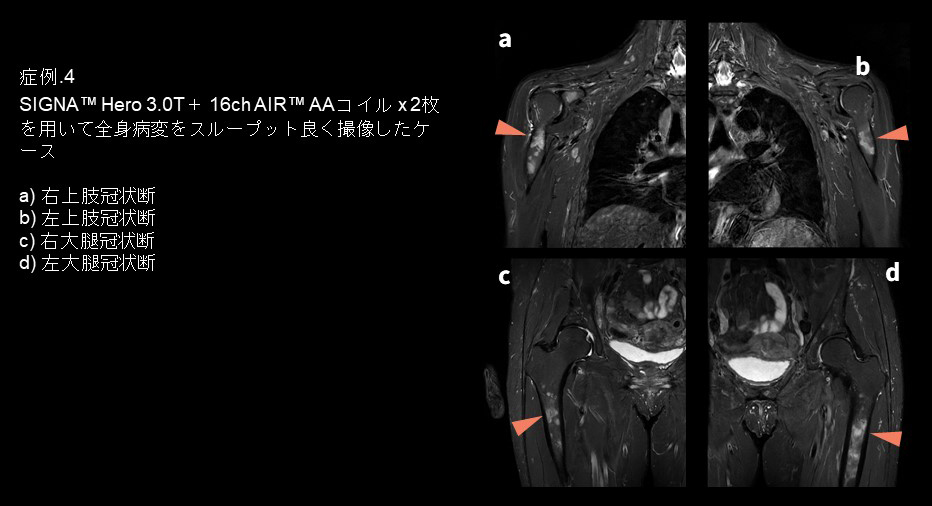

・症例4

サルコイドーシスの全身骨病変が存在する稀なケースで、そのフォローアップを行いました。全身骨病変が存在するため両上肢・両下肢の4部位を撮像する必要がありました。 従来であれば左右それぞれ身体を寄せて、撮像部位がボア中心なるように2回のポジショニングが必要になる検査です。しかし今回は16ch AIR™ AAコイル 2枚を上半身・下半身に置き、ポジショニングを変更することなく撮像することができました。これはSIGNA™ Hero 3.0Tがワイドボアであることと、ボア内の磁場均一性が良好なことが大きい要因となっています。ポジショニングを変更することなく撮像を行うことによりワークフローが向上し 、検査全体の時間短縮にも貢献しています。さらにコイルを2枚置いたとしても患者さんが閉塞感を感じにくいことも特徴です。